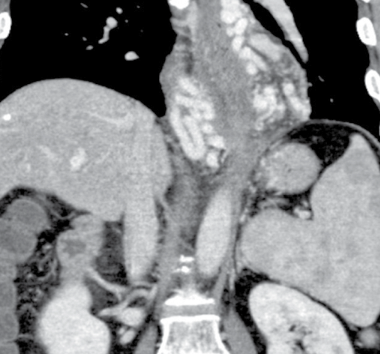

varices de l’oesophage voies voie de dérivation porto systémiques HTP